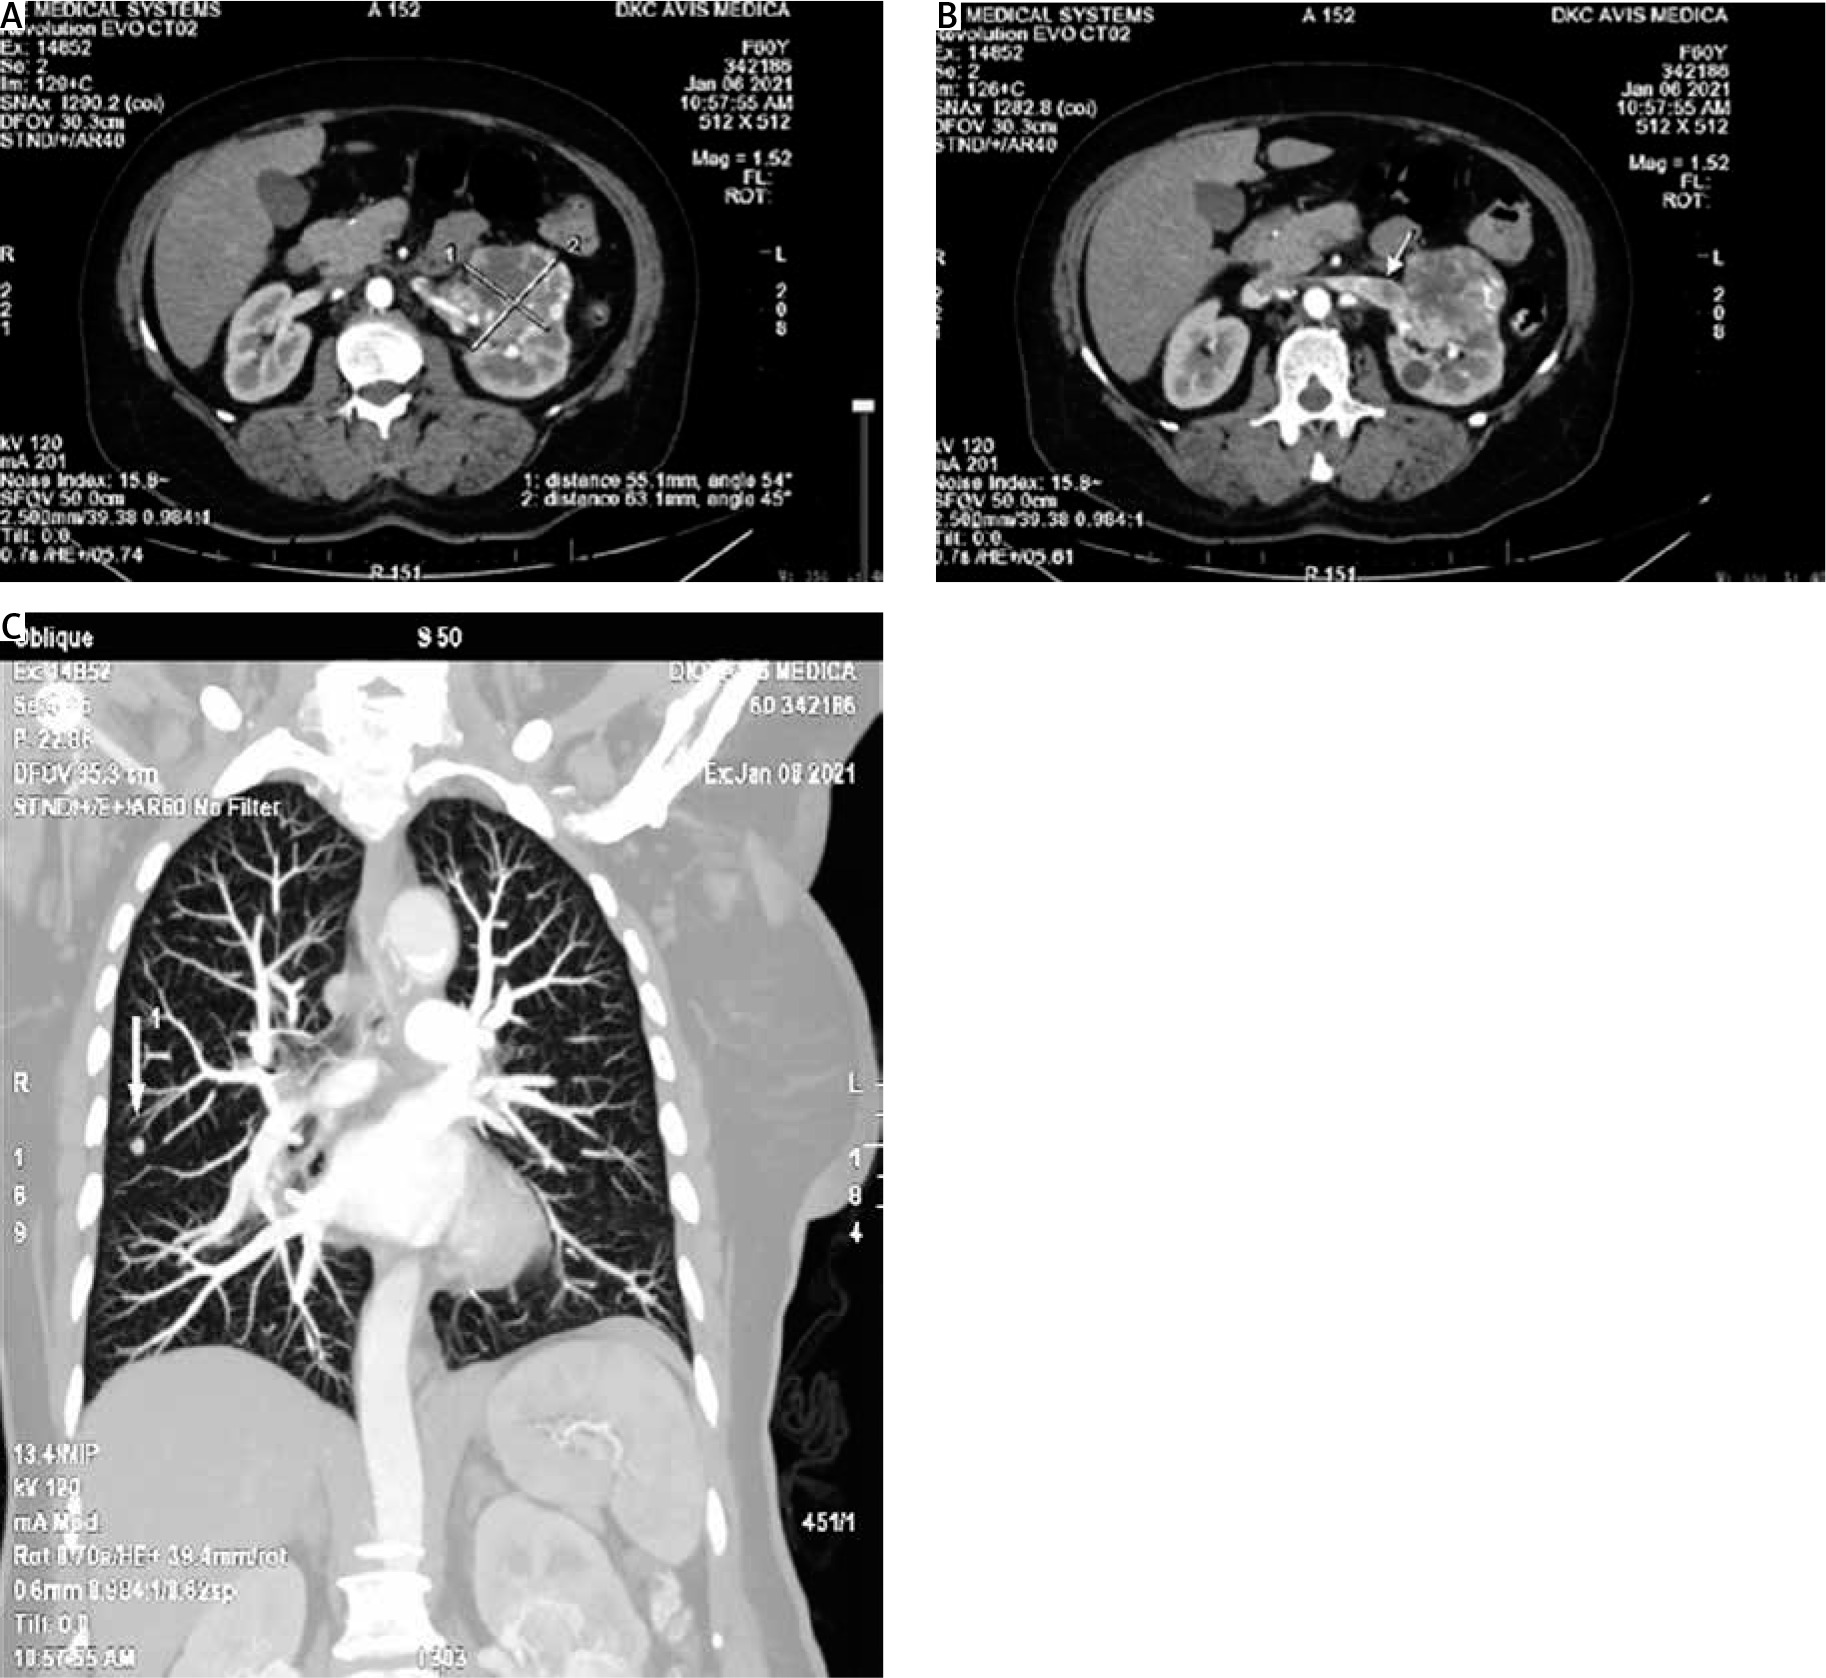

Postoperatively, a whole-body computed tomography (CT) was performed (because the removed formation did not appear like a primary carcinoma of the vagina). The computed tomography scan showed pathological changes in the left kidney and lungs. A lobulated, heterogeneous tumour formation in the middle third of the left kidney, measuring 63/55 mm (Fig. 2 A), and infiltration with tumour thrombosis of the left renal vein (Fig. 2 B) was manifested. In the lungs, bilateral, mostly apical nodular lesions up to 3 mm in size were detected. A solid nodule with dimensions of 7 mm was visualized along the right intralobular fissure (Fig. 2 C).

Fig 2

Computed tomography imaging. A) computed tomography finding with tumour formation; B) infiltration of the left renal vein with tumour thrombosis; C) solid nodule along the right intralobular fissure